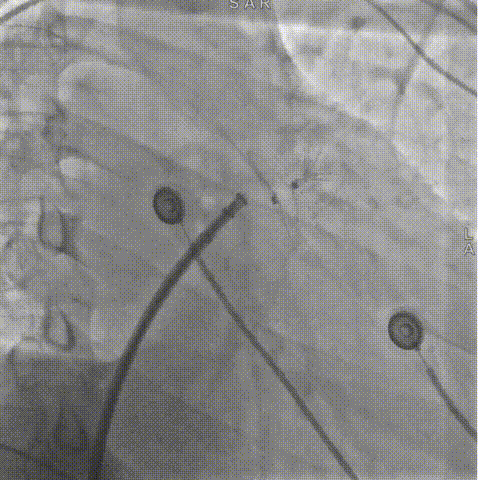

LAMax LAAC® 2430 Normal封堵器封堵盘在DSA下牵拉15s,锚定伞稳定无移位。

牵拉实验

锚定伞半释放造影

符合COVER原则,将LAMax LAAC® 2430 Normal封堵器释放,再次DSA造影检查,封堵器形态无变化,封堵效果好。